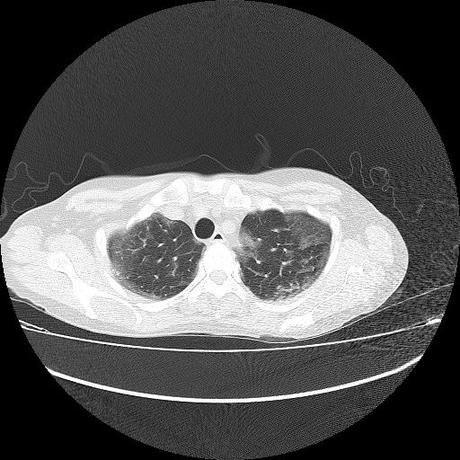

Se realiza volumen de tórax en fase simple, desde los opérculos torácicos hasta los hemidiafragmas, observándose:

El parénquima pulmonar con areas parcheadas difusas en vidrio despulido combinadas con otras areas hipodensas de baja atenuación debidas a atrapamiento aéreo y engrosamiento intersticial y zonas de fibrosis de predominio en lóbulos medios e inferiores de ambos pulmones.

- LOS HALLAZGOS PUEDEN ESTAR EN RELACIÓN A NEUMOPATIA INTERSTICIAL PROBABLE ETIOLOGIA HIPERSENSITIVA VS AUTOINMUNE/BACTERIANA/FUNGICA.